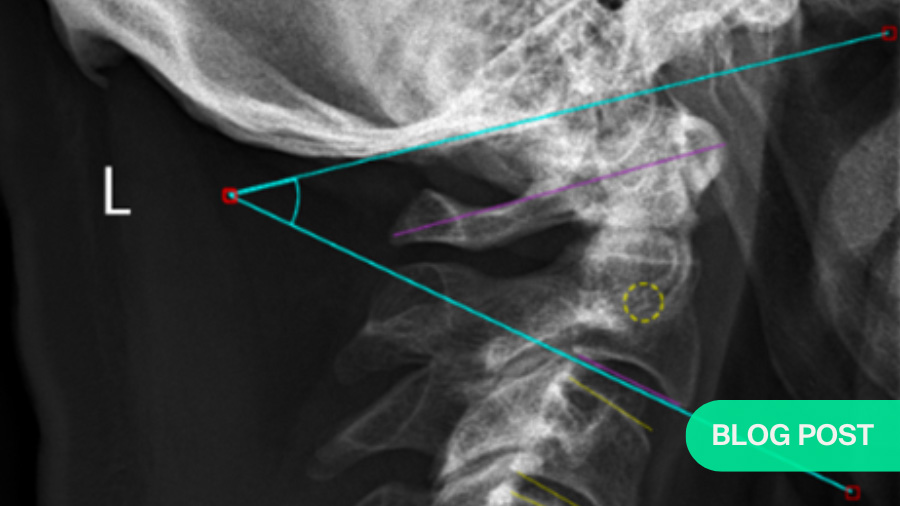

Cervical Subaxial Facet Injuries: evaluation, management, and how to use the AO Spine Classification System

BY DR RATKO YURAC AND DR ANDREI JOAQUIM